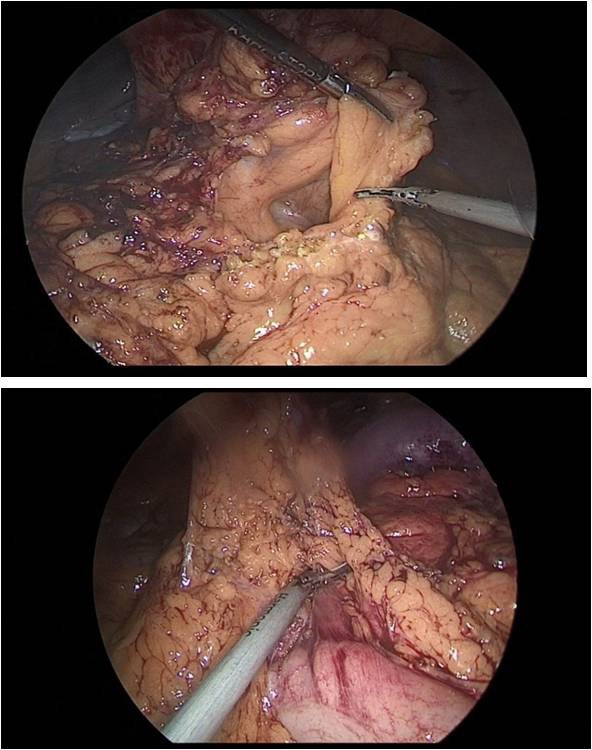

The stomach is mobilized to pyloric sphincter. Next, was performed mobilization along the lesser curvature of the stomach (Figure 8). For this, the lesser omentum was resected, lymph node dissection of I, III, V, VII groups of lymph nodes. The left gastric artery was clipped (Figure 6a,b) and transected (Figure 7).

Figure 6a,b: Resection of the lesser omentum with removed I, III, V, VII group of lymph nodes.

Figure 7: The left gastric artery was clipped with a Hemo-Lock (X) clip, with additional fixation with tantalum clips.